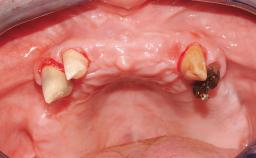

Rehabilitating an Edentulous Maxilla with a Fixed Dental Prosthesis Following Provisional Immediate Loading

This case features the flapless computer-guided placement of 7 bone-level implants, distributed to provide maximal support for the prosthetic framework. A rigid one-piece metallic framework was utilized as an interim restoration to reduce the risk of fracture associated with this prosthetic design. As part of the clinical examination, the SAC Assessment Tool was used, resulting in a surgical and restorative risk classification as “complex”.

Case Type Edentulous Maxilla

Jaw Maxilla

Area Full-Arch

# of Implants 7